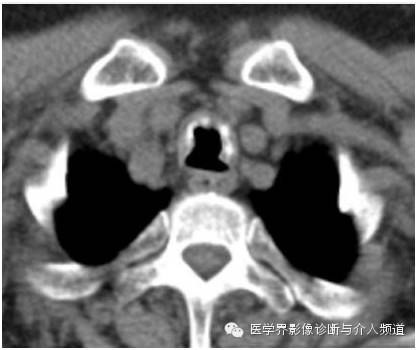

胸部CT平扫显示主支气管前壁及两侧壁可见多个钙化及未钙化的结节,后壁未见异常病变。支气管镜检如上图。

当CT发现多发性气管 、支气管壁增厚或管壁钙化灶时,在诊断中要注意 TO 和下列疾病相鉴别:气管支气管淀粉样变、多发性骨软骨炎、乳头状瘤、气管支气管内膜结核等。CT发现多发黏膜下小结节钙化并突向管腔,前壁及侧壁受累,后壁无异常这些征象是TO较具有特征性的CT表现,如CT上出现这些征象,应该首先考虑TO。

CT表现

CT主要表现为在气管支气管前壁和侧壁黏膜下散在或多发分布斑点钙化状小突起,突向管腔,大多数突起直径在 1~3 mm,但有的结节较大,达到10 mm。一般黏膜下高密度钙化状影和气管环不连接。

TO病变严重时,气管壁弥漫增厚,管壁塌陷,管腔缩小。当病变发生在叶支气管或段支气管时,常导致管腔狭窄,加上黏液栓塞,极易引起肺不张。病变主要发生在气管中、下段的前、侧壁,后壁一般不累及。但也有文献报道后壁也可见,主要发生在较严重的病例。

总之,TO是一种罕见疾病,临床症状不典型,因此对于怀疑TO患者,胸部CT扫描是非常必要的检查,如出现气管前壁及两侧壁黏膜不规则钙化,后壁正常,需高度怀疑TO,进一步的支气管镜和组织病理学检查可明确诊断。